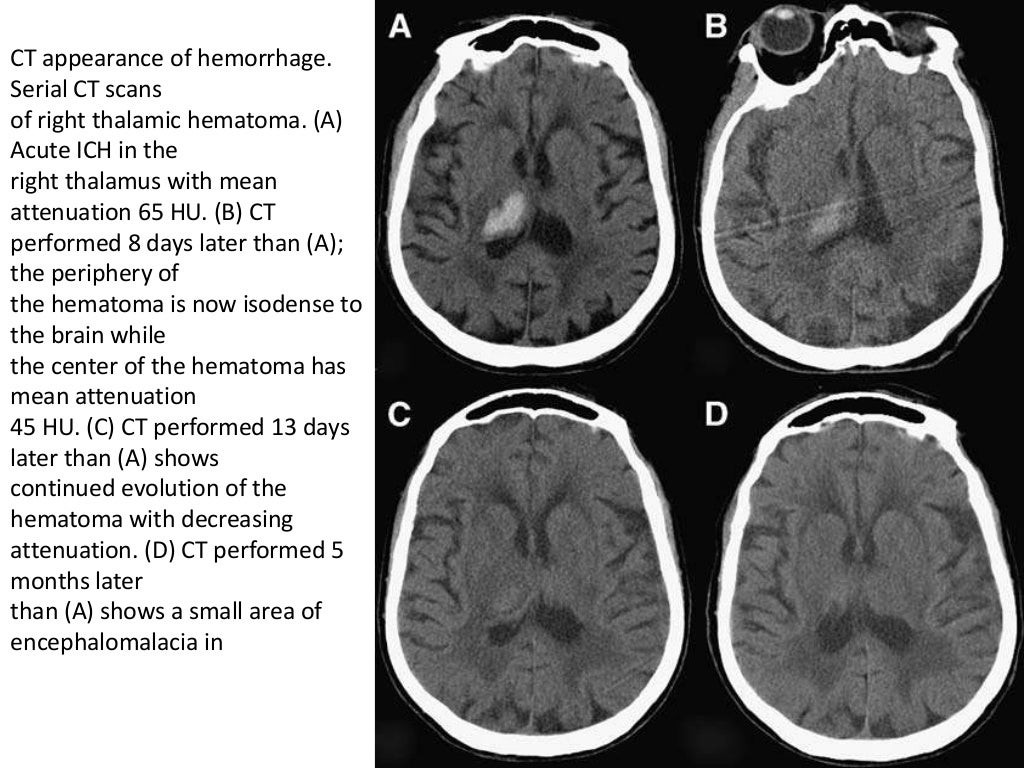

Radiology of Brain hemorrhage vs infarction Ct Scan Brain Bleed ct scan is almost always the first imaging modality used to assess patients with suspected intracranial. last update 11th dec 2020. intracranial hemorrhage comprises 4 broad types of hemorrhage, including epidural hemorrhage, subdural hemorrhage,. ct scan is almost always the first imaging modality used to assess patients with suspected intracranial. Identifying a unilateral hemorrhage within the. Ct Scan Brain Bleed.